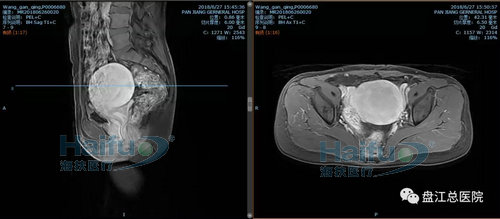

我院病例2:患者王XX,46歲,子宮腺肌癥患者。

因“發現盆腔包塊10+年,繼發性痛經2+年”入院。于2018年6月28日行高強度聚焦超聲消融治療(HIFU)。

治療經過:給予鎮靜鎮痛藥物后開始輻,患者訴稍有骶尾部及治療區脹痛不適,余未訴有不適,安靜休息配合治療。總治療時間25min。

術前磁共振增強橫斷位及矢狀位,見病灶內明顯強化

術后磁共振增強,見病灶內無明顯強化,病灶發生凝固性壞死